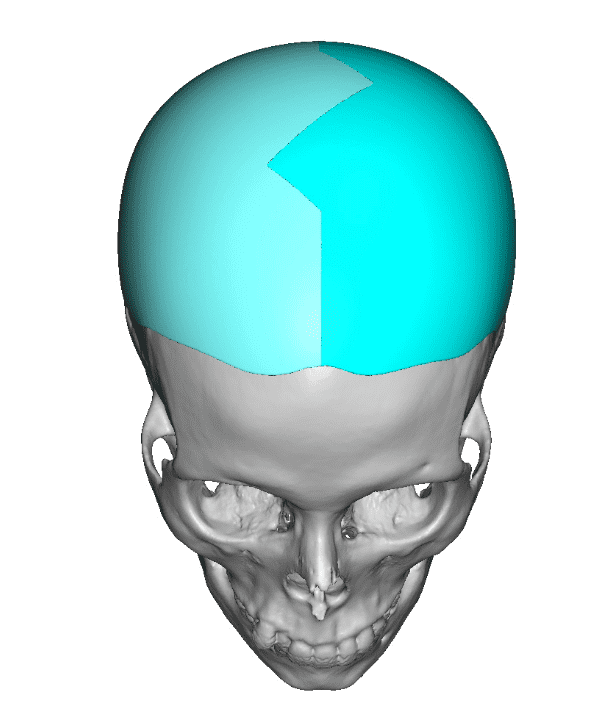

Desire for major head reshaping with a taler and wider head shape.

Placement of large two piece custom skull implant through a sagittal scalp incision.

Desire for major head reshaping with a taler and wider head shape.

Placement of large two piece custom skull implant through a sagittal scalp incision.